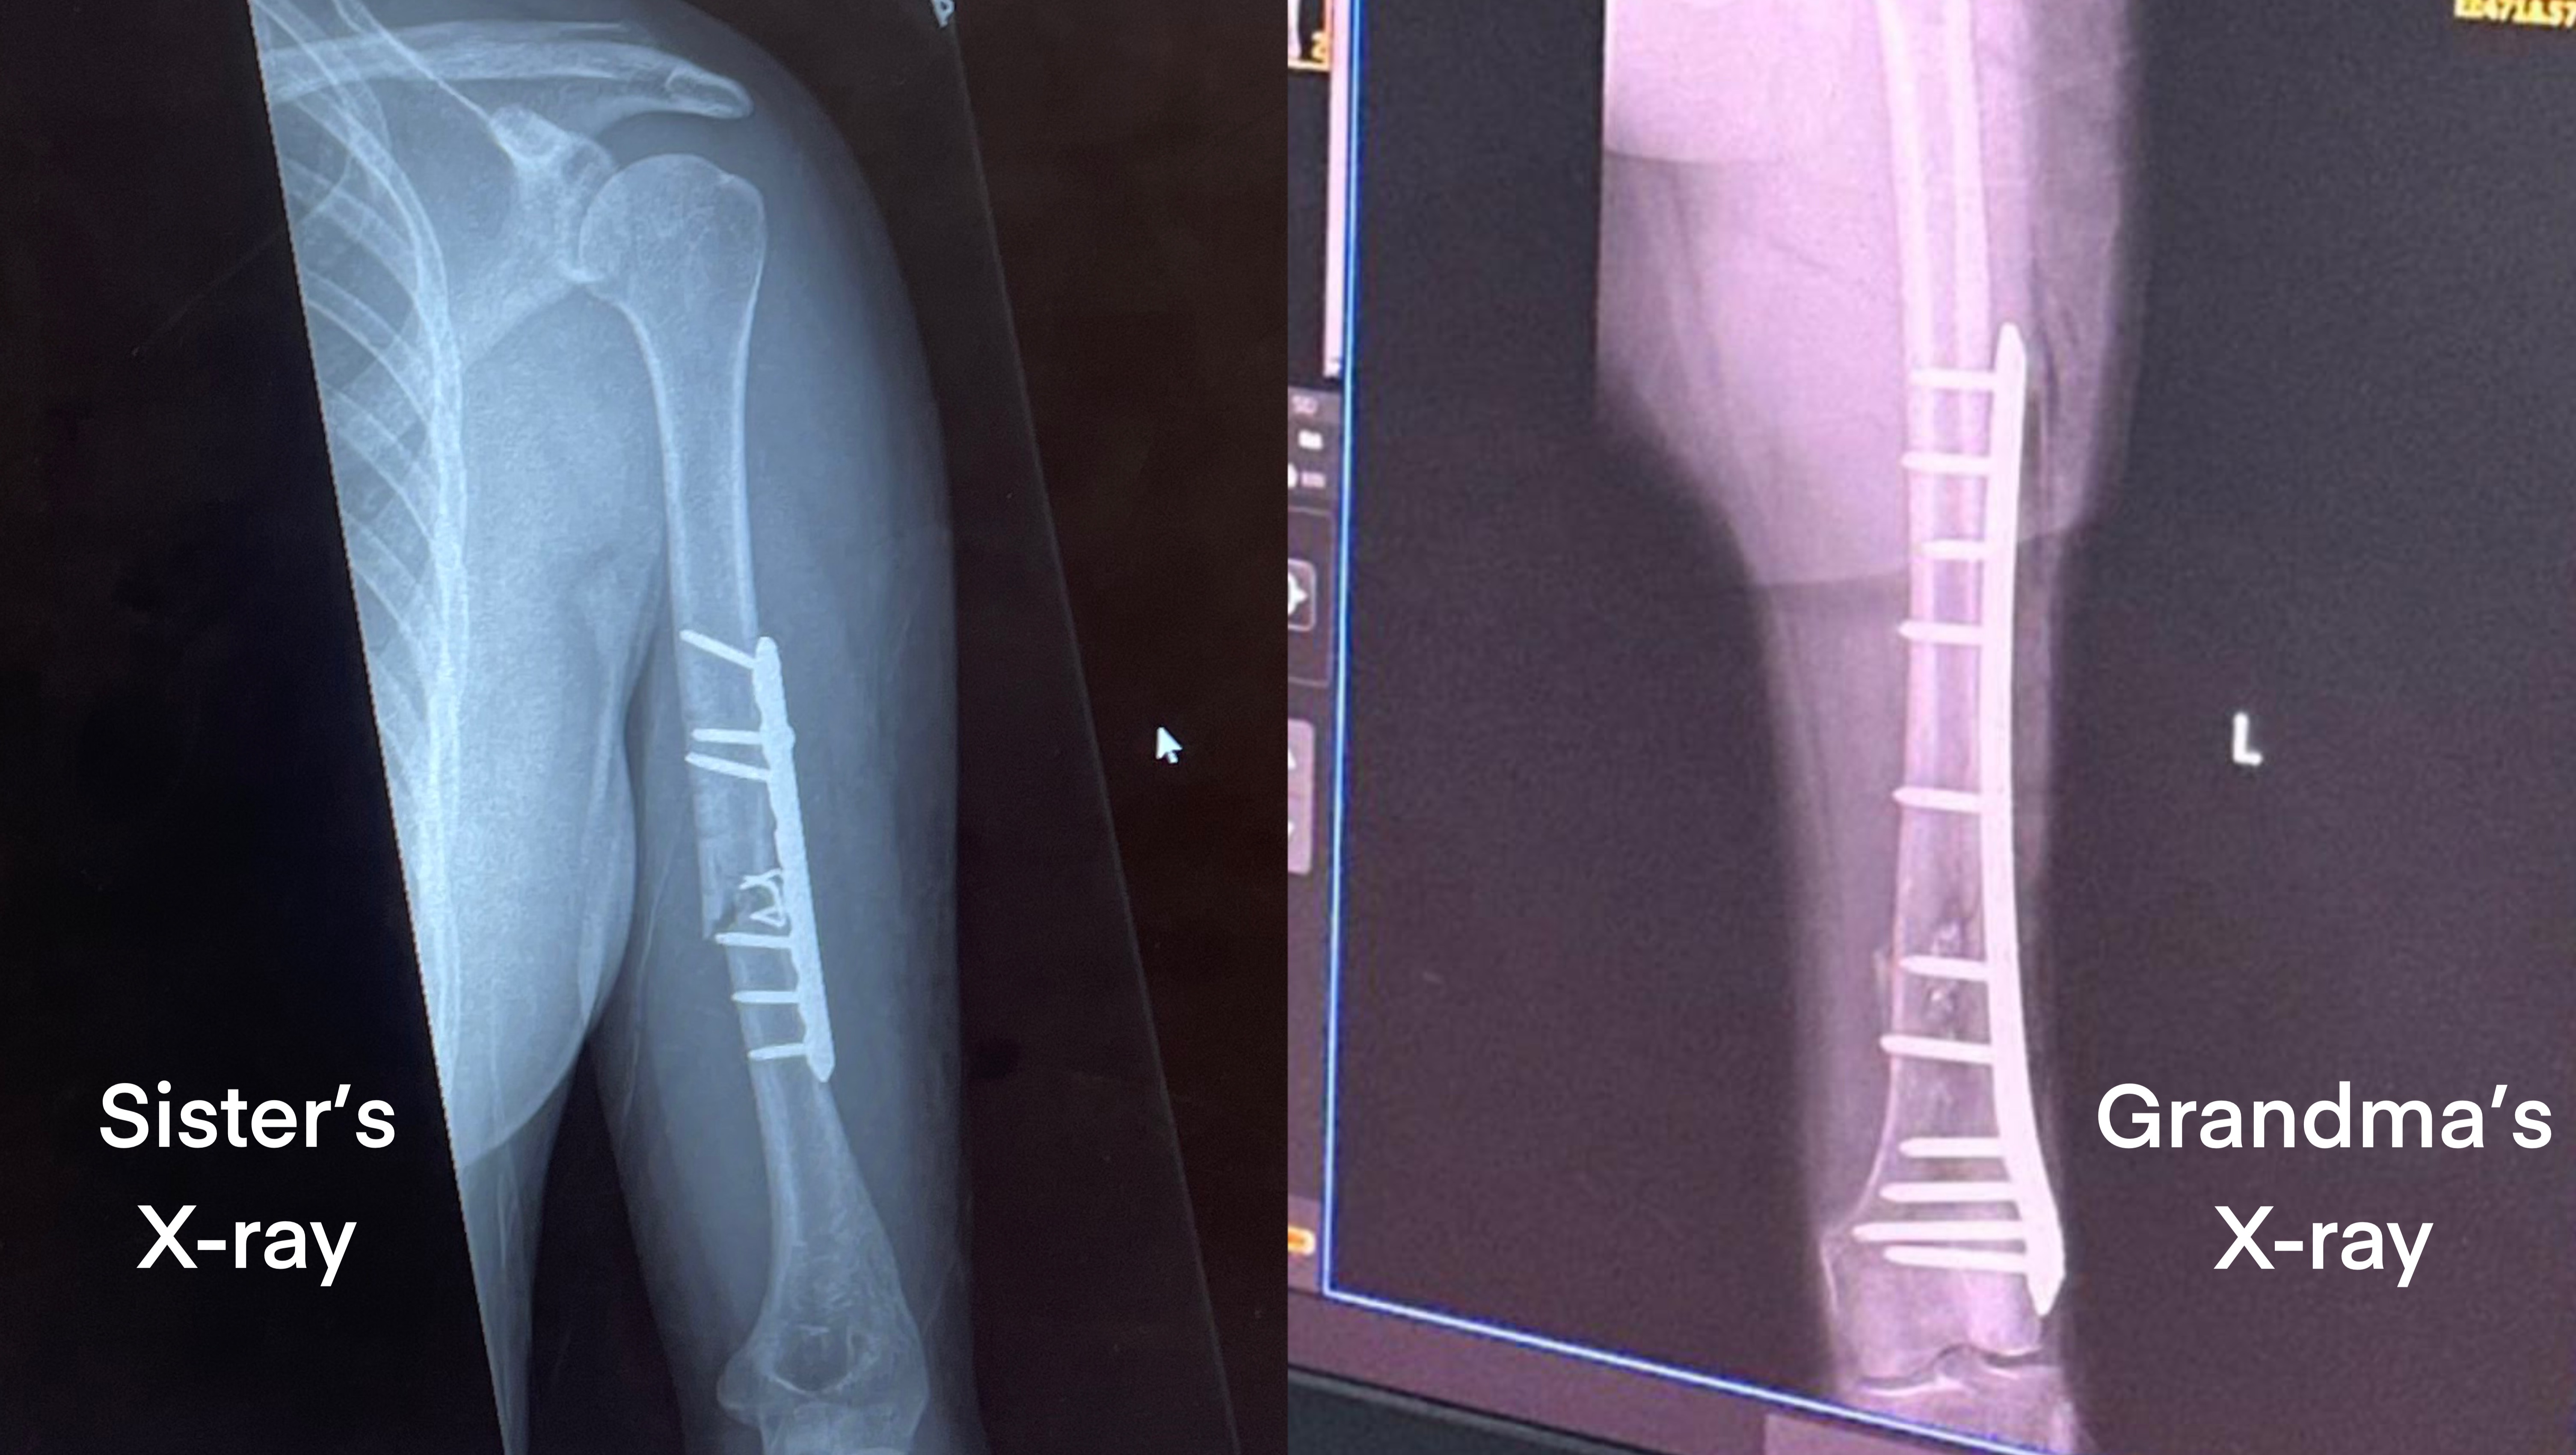

On January 26, my sister fell and broke her arm in New York a few days before our mom was supposed to fly in from Jakarta, Indonesia. On January 28, my grandma fell and broke her leg in Jakarta. Both required surgery and hospitalization.

My sister and grandma's surgeries were successful but also very costly (especially if we include the extensive physical therapy they would both have to go through). My mom bears the majority of our family's financial responsibilities. She is a single mother who has to work 70+ hours a week to support her family, acting as our grandma's main caretaker and regularly helping both me and my sister when our own income falls short of making rent.

My grandma's medical expenses: IDR 189,684,740/~USD 11,860

- Lab & Radiology (IDR6,160,000/~USD390)

- Surgery (IDR35,700,000/~USD2,230)

My sister's medical expenses: ~USD $2,000-3,000